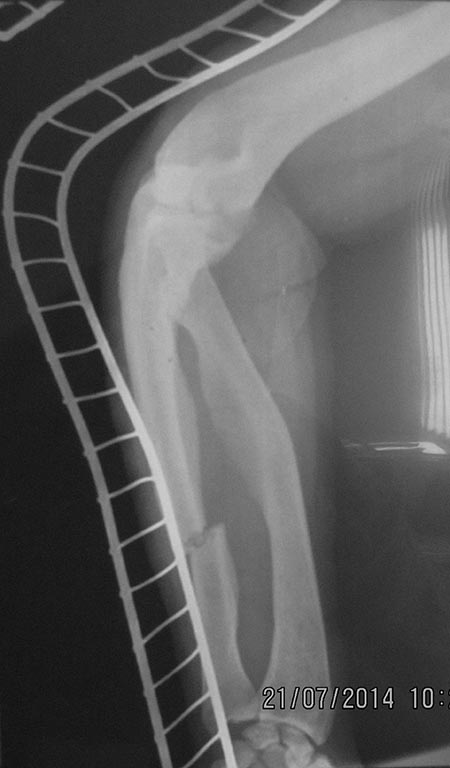

[Ortho] перелом бедра с исходной деформацией

Выкладываю, как и обещал. За репозицию педплечья не осуждайте!